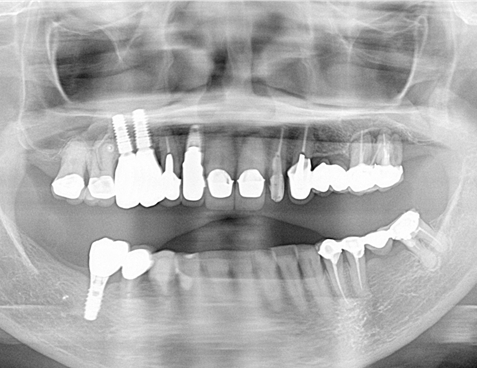

レントゲン写真でも理想的な位置

に埋入できました。

術前ではインプラントを埋入する骨組織はほとんど有りませんが、

術後完全に骨内に埋入出来ました。